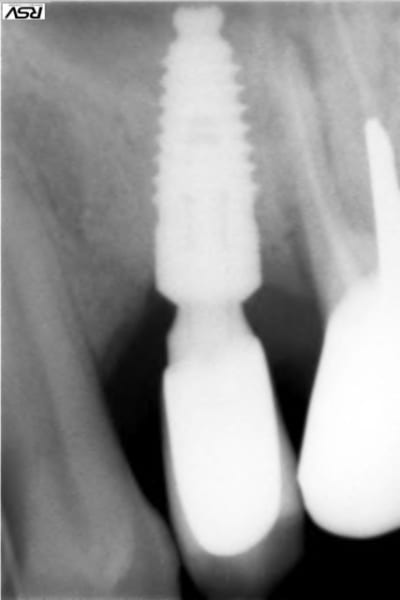

Présentation du cas : extraction de 26 , attente 2 mois cicatrisation, hauteur résiduelle estimé à 5 mm , mauvaise surprise après avoir oté le provisoire, très belle crète bien large mais invaginée en son centre.

Forage au milieu à 3mm + effraction du plancher ,manoeuvre de Walsava OK, bourrage au Gen Oss (0.5cc) , re Walsava, et implant IDCAM 10/5.2 bloqué au maximum .

oups , les photos de ce matin.

sur la radio post-op, l'espace entre l'implant et la pré-molaire, non comblé, ne causera pas de problème ?

J'aurais tenter un SA-3, pour comblé plus large et évité ce vide, qui est un ramasse bactérie dans le sinus...

pour céramik

peut être , mais je parie plutot sur une remontée générale du plancher dans ce secteur, vu la faible distance avec la prémolaire.

Tiens jette un coup d'oeil sur la partie mésial de cet implant sans comblement où 3 spires ont été englouties dans la cicatrisation osseuse